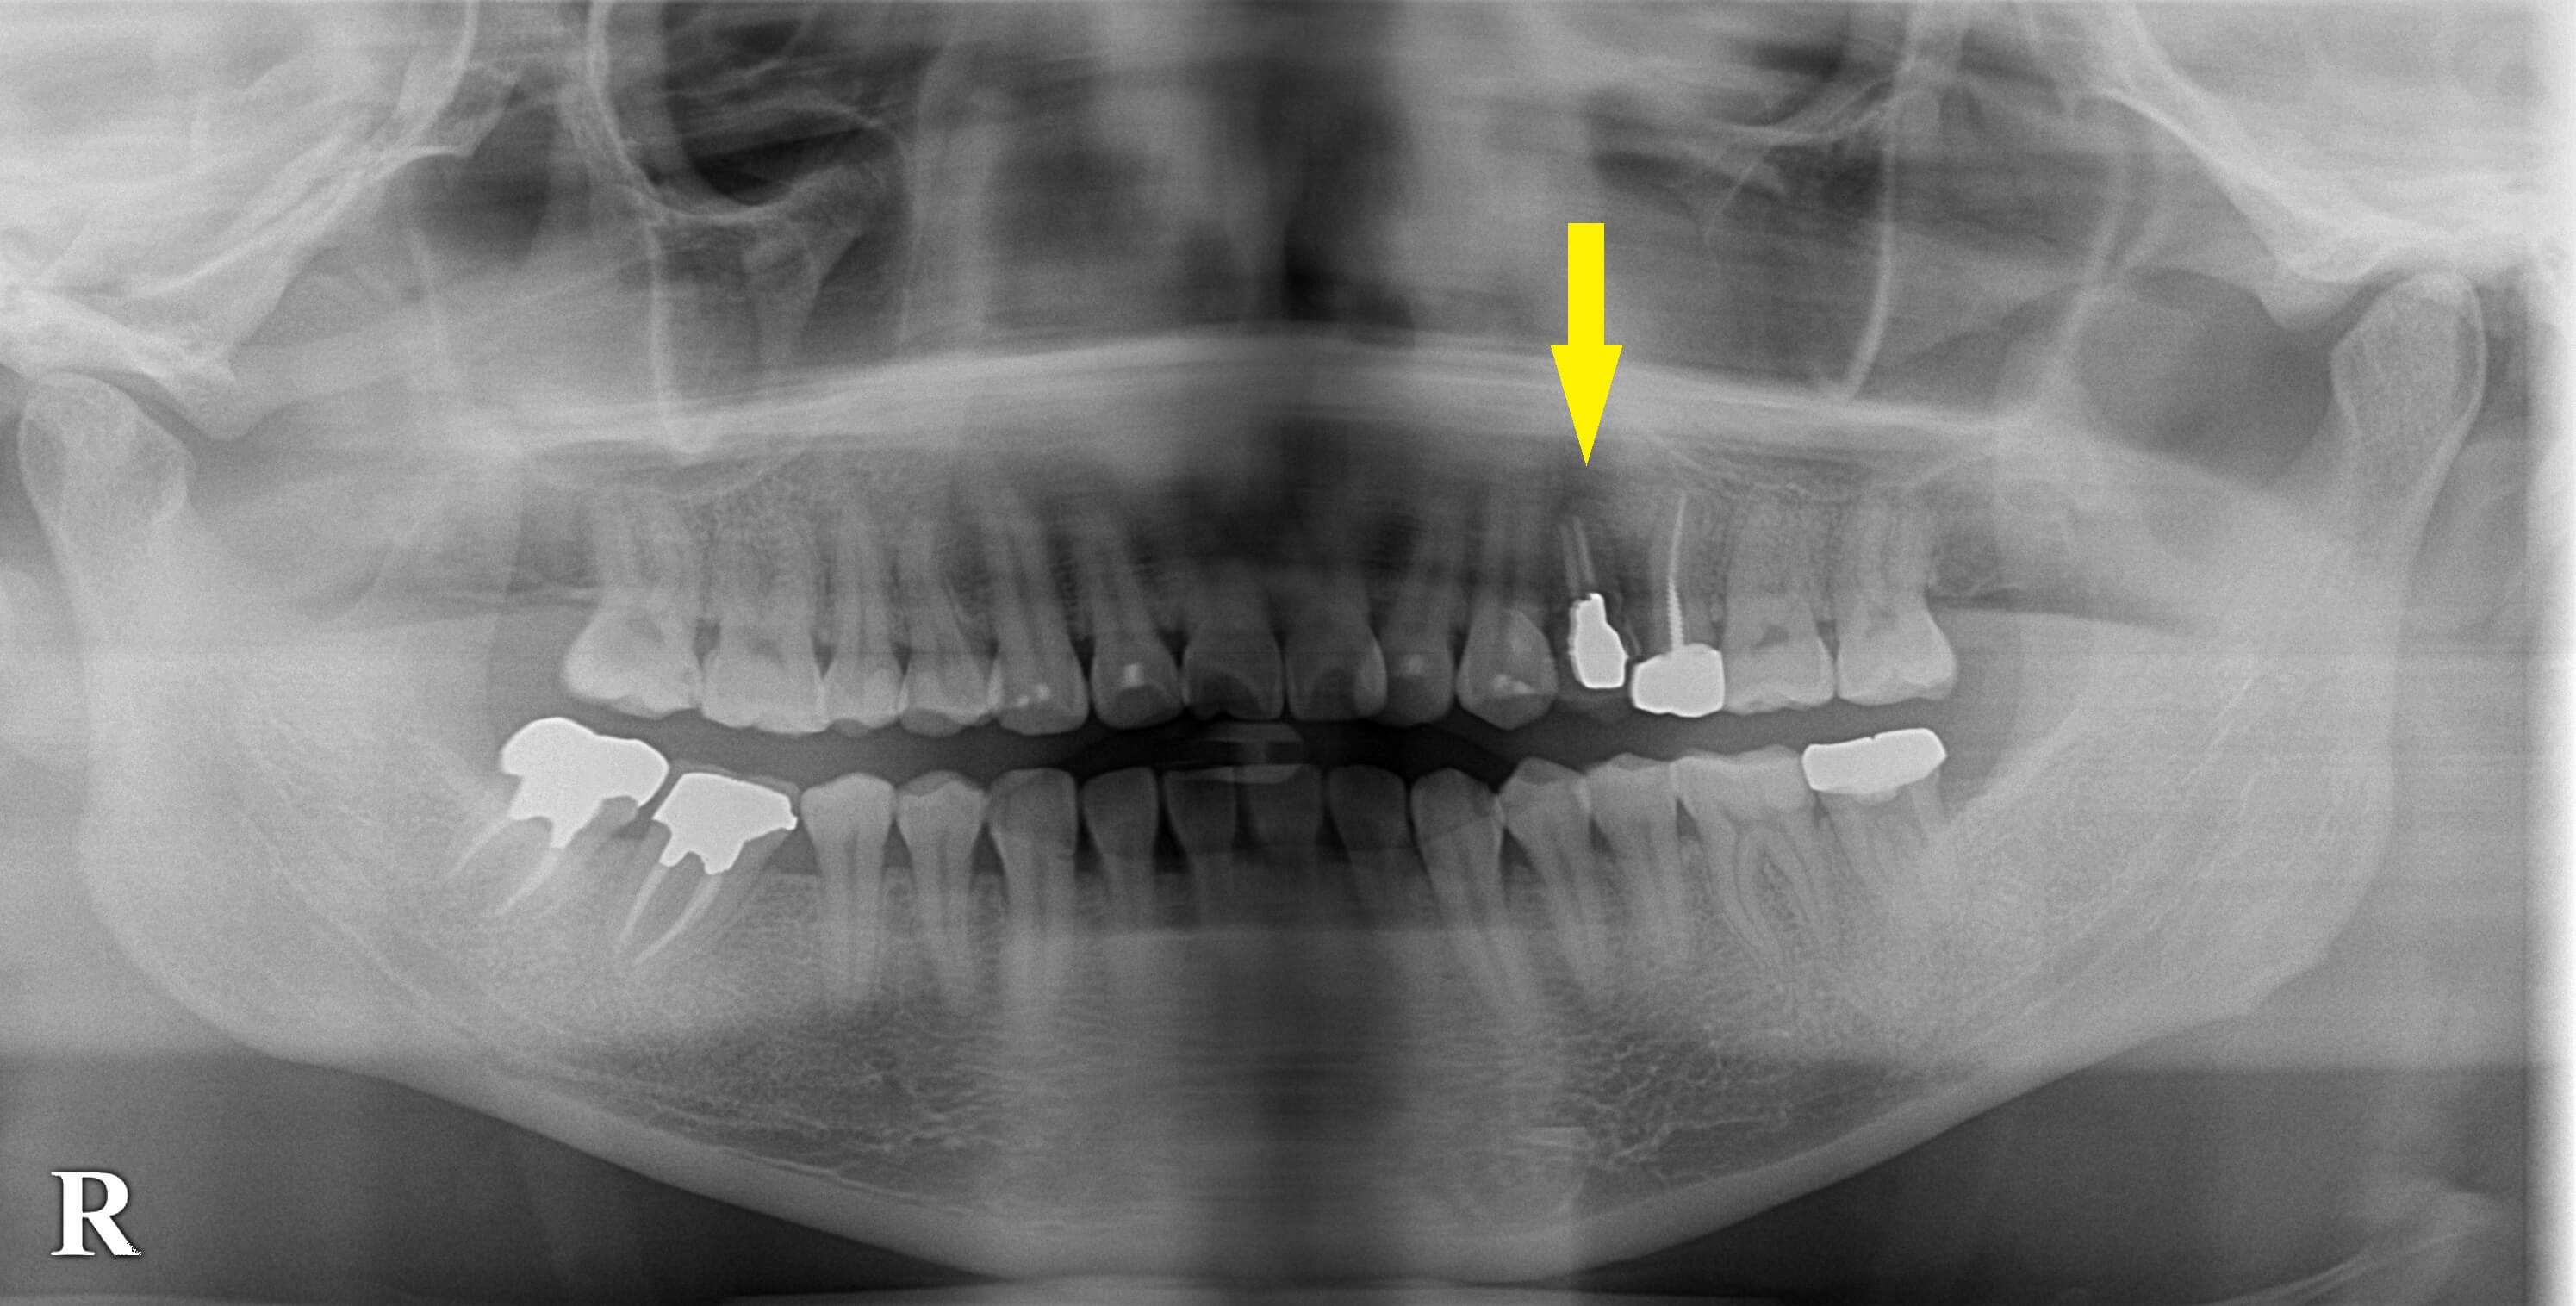

1歯欠損、歯を削るブリッジよりもインプラントで 今週のインプラント症例 2022.02.182026.01.19 患者様は名古屋在住の30代女性。 左上顎の第一小臼歯が破折を起こし、他院にて、抜歯しなければならないと説明を受けたそうです。 その歯科医院ではインプラント治療を行っていないため、前後の歯を削ってブリッジにすると言われたそうです。 前方の犬歯は、健全なので削りたくないということで、インプラント治療を希望されて当院に相談に来られました。 レントゲン、CTにて骨量に問題はありませんでしたので、当院にて抜歯、本日インプラント埋入術を行いました。 症例・コラム一覧に戻る